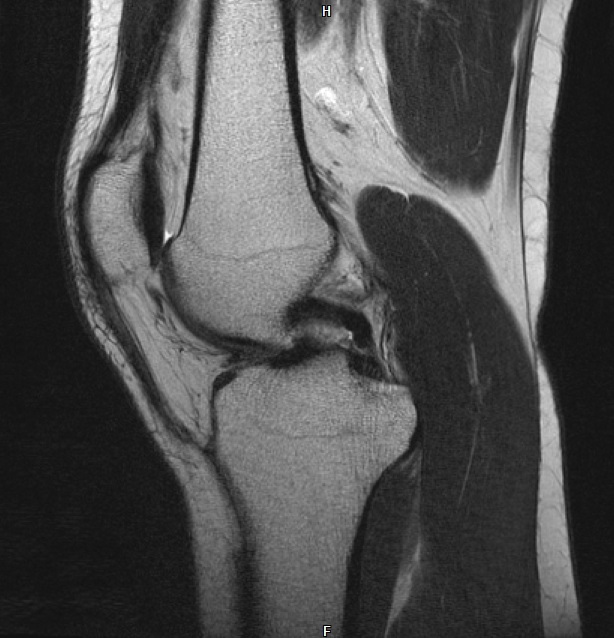

Ich war gerade im MRT wegen Problemen mit meinem rechten Knie. Hab jetzt kurz mal einen auf Dr. Google gemacht und Bilder der häufigsten Verletzungen verglichen mit meinen Bildern. Da bin ich beim vorderen Kreuzbandriss etwas aufmerkasm geworden. Das sind meine Bilder

auf dem letzten Bild sieht man mein hinteres Kreuzband ja wunderbar, es ist ja dieser dunkle "Haken", der Oberschenkel und Schienbein miteinander verbindet.

Nun aber auf dem 3. Bild sollte man doch dasselbe fürs vordere sehen? Aber ich sehe da nur die Ansätze am Schienbein?